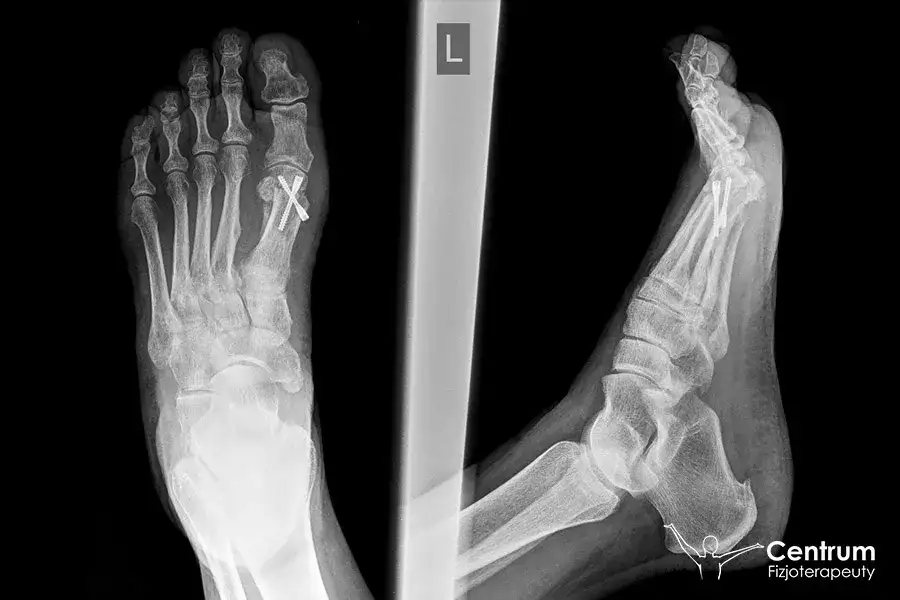

Dowiedz się, kiedy operacja haluksów jest konieczna. Poznaj objawy, proces kwalifikacji i metody leczenia zachowawczego i operacyjnego. Sprawdź, czy to czas na zabieg!

Poznaj haluksy: przyczyny, objawy i skuteczne metody leczenia od zachowawczych po operacyjne. Dowiedz się, jak rozpoznać paluch koślawy.

Jak wygląda haluks? Zobacz zdjęcia, rozpoznaj objawy (ból, guz) i przyczyny (genetyka, buty). Odkryj, jak zatrzymać jego postęp.